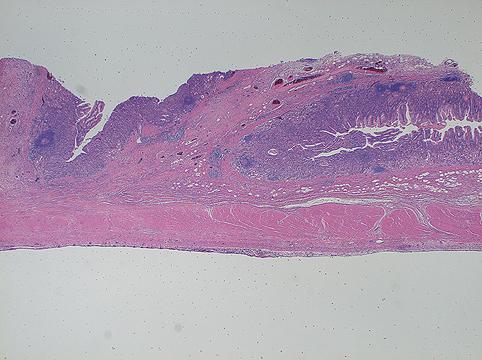

疾病(病理主体)的分类恶性上皮性肿瘤/腺癌

部位(按器官分)胃(部位)/胃角

检查方法病理切片(微观)

肿瘤的肉眼分类0型(表在型)/IIc型(IIc)

肿瘤最大直径10~14

肿瘤的深度m